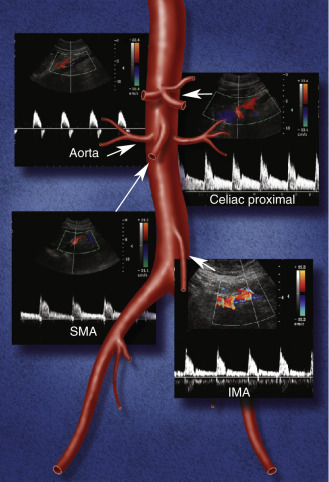

El color doppler imaging o CFM: color flow mapping Codifica la velocidad media del flujo sanguíneo en colores, de acuerdo a una determinada escala, superponiéndola a la imagen Modo B (bidimensional en blanco y negro). La zona de muestreo está determinada por el ROI (caja de color).

El color muestra la dirección del flujo. El del margen superior de la columna siempre representa el flujo hacia el transductor y el contrario el flujo que se aleja del transductor. Mientras mayor sea la velocidad, el color es más brillante.

La ecografía Doppler abdominal en neonatos se utiliza para evaluar el flujo sanguíneo en diversas arterias abdominales, principalmente la arteria mesentérica superior (SMA) y el tronco celíaco. Los parámetros de esta técnica incluyen la velocidad sistólica máxima, la velocidad diastólica final, el índice de pulsatilidad (PI) y el índice de resistencia (RI), que son cruciales para detectar condiciones como la enterocolitis necrosante (NEC) en neonatos.[1-2]